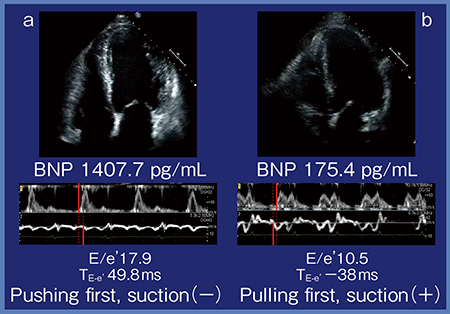

症例1(図2 a)は,46歳,男性,拡張型心筋症(DCM)症例で,EFは25%である。症例2(図2 b)は,64歳,男性,冠動脈バイパス術(CABG)後症例で,EFは30%である。心尖部から観察した超音波画像では,どちらの症例もほぼ同じように動きが悪いように見える。症例1は,BNPが1407.7pg/mLと非常に高値で心不全症状も強い。一方,症例2は,BNPは175.4pg/mLとそれほど高くなく,心不全症状もほとんど見られない。この2症例をDual Gate Dopplerで見ると,症例1はE波が高く,e’波は低く,E/e’が17.9と上がっている。症例2は,e’波も比較的保たれており,E/e’は10.5であった。これだけであればSingle Doppler法のE/e’でもわかるが,Dual Gate Dopplerではよく見ると,症例1ではE波の方が速く,Pushing firstであり,suctionのない症例と言える。一方,症例2はe’波の方が明らかに速く,E/e’は10.5であるがE波からe’波までの時間(TE-e’)が−38msで,Pulling firstであり,suctionのある症例と言える。

図2 Dual Gate Dopplerを用いたE/e’測定の実際

a:症例1(46歳,男性,DCM,EF25%)

b:症例2(64歳,男性,CABG後,EF30%)